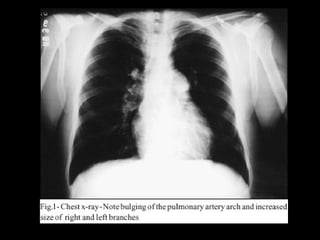

ARTERIA PULMONAR Proyección PA Su dilatación se manifiesta por abombamiento del arco de la pulmonar. Proyección OAD Una prominencia entre el arco ventricular y la aorta ascendente.

ARTERIA PULMONAR ProyecciónPA Su dilatación se manifiesta por abombamiento del arco de la pulmonar. Proyección OAD Una prominencia entre el arco ventricular y la aorta ascendente.